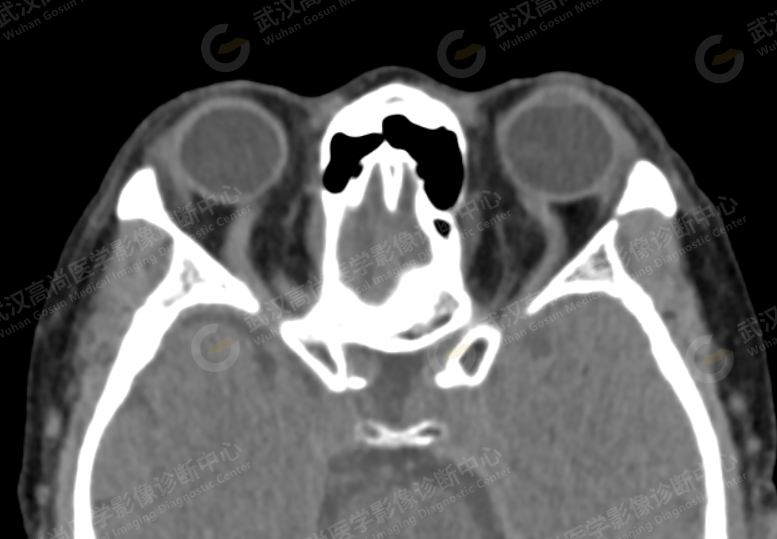

头颅 CT 平扫未见明显异常,眼眶薄层 CT 图像所示:

双侧眼球轻度向前突出,眼球大小及形态无异常,双眼内直肌肌腹轻度增粗,双侧眼上静脉对称性轻度增粗,边缘清晰,走行较迂曲。询问病人及家属得知半年前可能头部外伤,但不能肯定。

1、双侧眼上静脉对称性增粗,建议结合临床,进一步检查;

2、双侧眼球轻度突出,双眼内直肌肌腹轻度增粗,请结合临床;